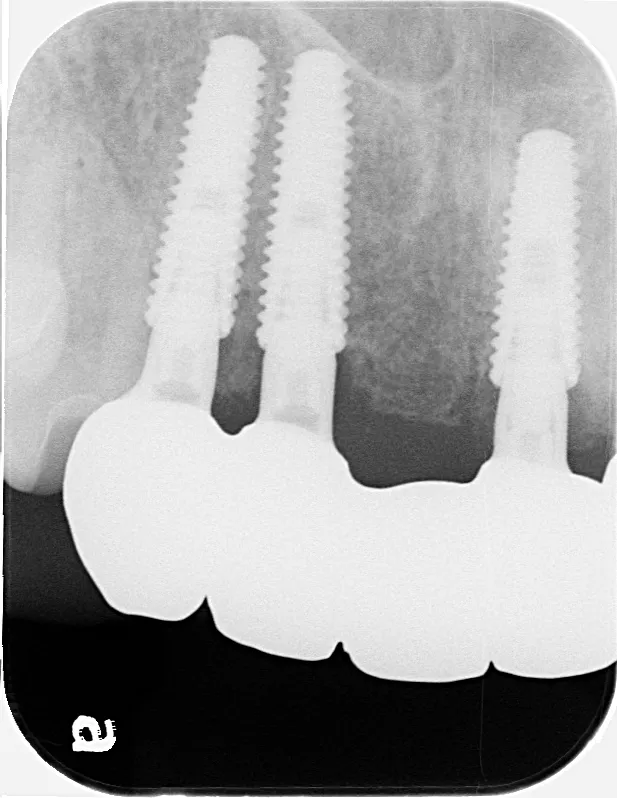

治療内容

左下67 欠損に対してインプラント治療を行った症例

部分床義歯を使用していたが、どうしても慣れない上にしっかり噛むことができないためインプラント治療を希望